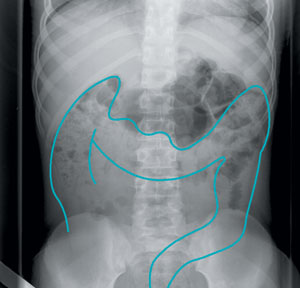

The physical examination should focus particularly on the abdomen, spine and perineum. The abdominal examination reveals whether there is a significant colonic mass. Of all children with significant constipation, about half will have palpable abdominal stool.22

An abdominal x-ray is only likely to be useful if no significant faecal retention is found on rectal examination.24 There can be considerable interobserver variation among radiologists in scoring x-rays for faecal retention.23 Agreement is more likely with a large amount of retained faeces.

There is considerable interobserver variation in the interpretation of abdominal x-rays investigating faecal retention (III-2).23